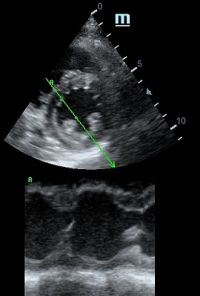

Но как же провести стандартные измерения в М-режиме, если мы его не использовали? На помощь приходит функция Free Xros M – анатомический М-режим. Имея записанную в память прибора видео петлю, мы можем провести линию М-режима в любом месте, при этом корректируя изначально не оптимальный угол.

Возможности применения функции многогранны: от измерения толщины стенок левого желудочка, движения створок митрального клапана и кооптации нижней полой вены до оценки сократимости миокарда как глобально, так и по сегментам.

TAPSE - показатель амплитуды движения латеральной части кольца трикуспидального клапана, позволяет количественно и быстро оценить систолическую функцию правого желудочка, норма которого составляет более 17 мм. Главным условием является проведение линии М-режима параллельно стенке правого желудочка в апикальном четырех камерном сечении, что легко достигается при Free Xros.

MAPSE - амплитуда движения латерального кольца митрального клапана, позволяет рассчитать фракцию выброса по формуле EF = 4.8 × MAPSE (mm) + 5.8, очень быстрый и гораздо более точный («прародитель Strain») метод чем широко распространенный метод Teicholtz. В современных приборах можно легко добавить свою формулу при отсутствии ее в стандартном калькуляторе. Главным условием является проведение линии М-режима параллельно стенке левого желудочка в апикальном четырехкамерном сечении, что легко достигается при использовании функции Free Xros.